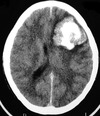

Quais os achados radiológicos?

Qual a principal hipótese diagnóstica?

herniação subfalcina, lesão hipodensa em lobo frontal e parietal direitos, efeito de massa sobre o ventrículo direito com desvio da linha média à esquerda